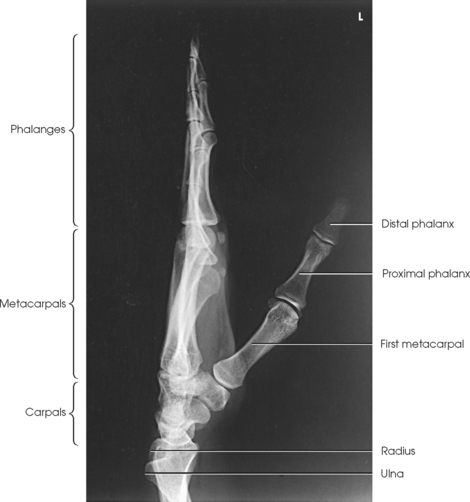

The hand consists of 27 bones, which are subdivided into the following groups:

• Phalanges: Bones of the digits (fingers and thumb)

• Metacarpals: Bones of the palm

• Carpals: Bones of the wrist (Fig. 4-1)

The digits contain 14 phalanges (phalanx, singular), which are long bones that consist of a cylindric body and articular ends. Nine phalanges have two articular ends. The first digit has two phalanges—the proximal and distal. The other digits have three phalanges—the proximal, middle, and distal. The proximal phalanges are the closest to the palm, and the distal phalanges are the farthest from the palm. The distal phalanges are small and flattened, with a roughened rim around their distal anterior end; this gives them a spatulalike appearance. Each phalanx has a head, body, and base.

Five metacarpals, which are cylindric in shape and slightly concave anteriorly, form the palm of the hand (see Fig. 4-1). They are long bones consisting of a body and two articular ends—the head distally and the base proximally. The area below the head is the neck where fractures often occur. The first metacarpal contains two small sesamoid bones on its palmar aspect below the neck (see Fig. 4-1). A single sesamoid is often seen at this same level on the second metacarpal. The metacarpal heads, commonly known as the knuckles, are visible on the dorsal hand in flexion. The metacarpals are also numbered 1 to 5, beginning from the lateral side of the hand.

The wrist has eight carpal bones, which are fitted closely together and arranged in two horizontal rows (see Fig. 4-1). The carpals are classified as short bones and are composed largely of cancellous tissue with an outer layer of compact bony tissue. These bones, with one exception, have two or three names; this atlas uses the preferred terms (see box). The proximal row of carpals, which is nearest the forearm, contains the scaphoid, lunate, triquetrum, and pisiform. The distal row includes the trapezium, trapezoid, capitate, and hamate.

The forearm contains two bones that lie parallel to each other—the radius and ulna. Similar to other long bones, they have a body and two articular extremities. The radius is located on the lateral side of the forearm, and the ulna is located on the medial side (Figs. 4-4 and 4-5).